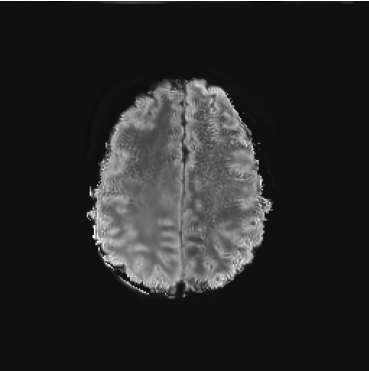

We also test our approach on healthy samples. Ideally, we would like our generative process to act as the identity function when given a normal image as input. Some examples are shown in Figure 6, where we can observe that the changes introduced by our sampling technique are relatively minimal and Dif-fuse preserves the structure and general appearance of the images.